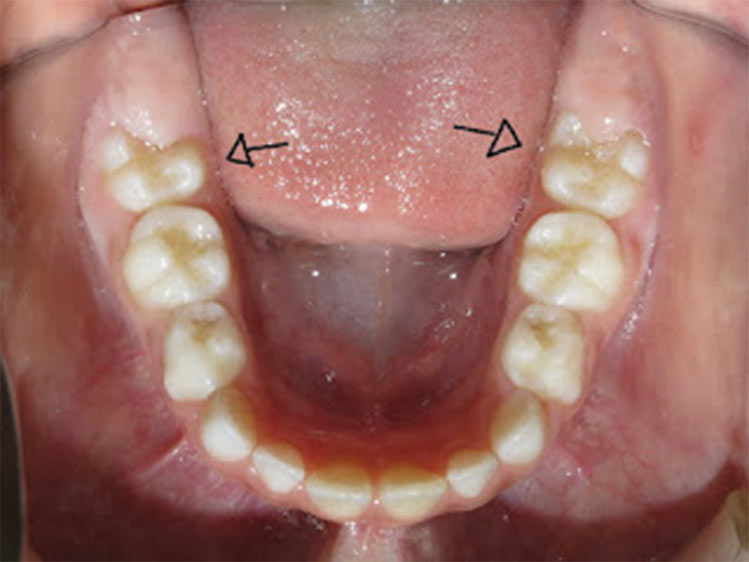

É necessário fazer uma avaliação clínica e radiográfica criteriosa da oclusão do paciente.

Porque dentes apinhados acumulam mais alimentos, mais placa bacteriana, mais tártaro, mais inflamação de gengiva, sangramento, mau hálito e aumentando o risco de surgimento de cáries.